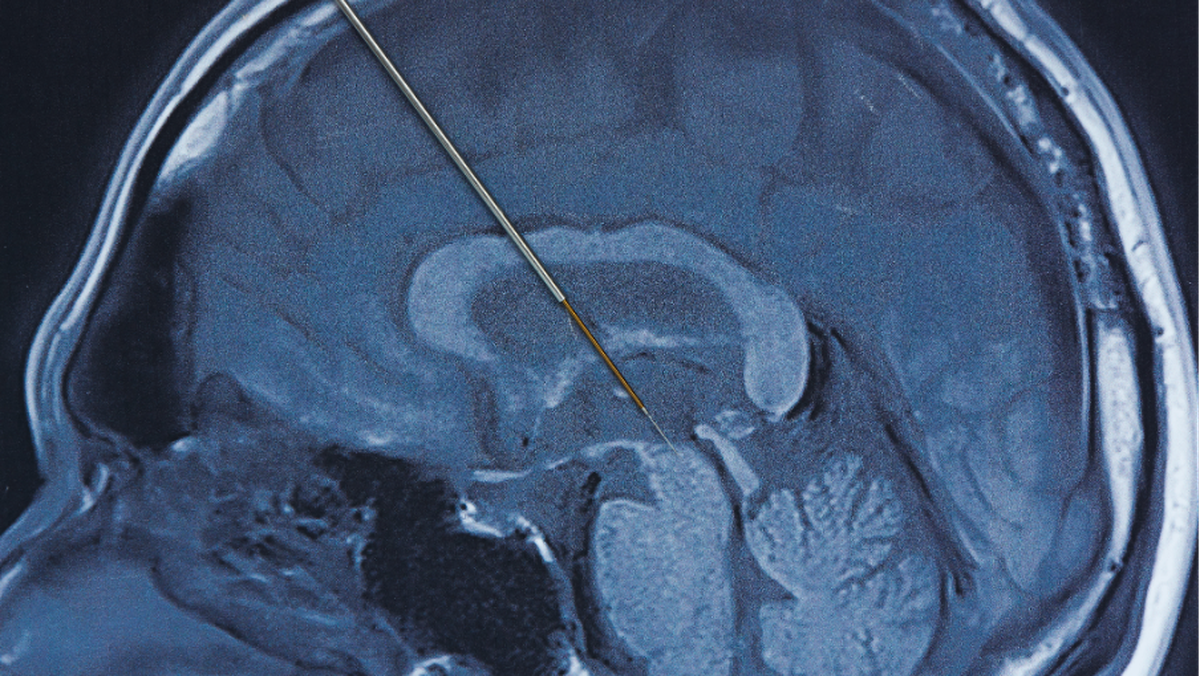

Deep brain stimulation merupakan prosedur bedah saraf yang melibatkan pemasangan elektroda Di area tertentu otak Untuk Memberi rangsangan listrik terkontrol. Stimulasi ini bertujuan mengatur kembali sinyal saraf yang terganggu akibat Gangguan Parkinson.

Praktisi Medis spesialis saraf Di Siloam Hospitals Kebon Jeruk, dr. Frandy Susatia, Sp.S, RVT, menjelaskan bahwa elektroda tipis ditanam Di otak dan dihubungkan Di Gadget stimulasi menyerupai alat pacu jantung. Gadget ini dipasang Di bawah kulit dada Dibagian atas dan bekerja secara terus-menerus mengirimkan impuls listrik sesuai pengaturan Praktisi Medis.

Tahap pertama adalah pemasangan elektroda Di otak Didalam bius lokal agar pasien tetap sadar. Di tahap ini, Praktisi Medis dapat Menimbang ketepatan lokasi elektroda Melewati simulasi yang diberikan, sambil pasien diminta Untuk Memberi umpan balik Yang Terkait Didalam perubahan Tanda-Tanda yang dirasakan. Sesudah lokasi dan jumlah stimulasi yang optimal ditemukan, proses pemasangan Gadget DBS secara permanen Akansegera dilakukan.

Tahap kedua dilakukan Didalam bius umum Untuk menanam Gadget stimulasi permanen Di bawah kulit dada Dibagian atas. Elektroda Di otak Lalu dihubungkan Di Gadget tersebut Melewati kabel halus yang dipasang Di bawah kulit.